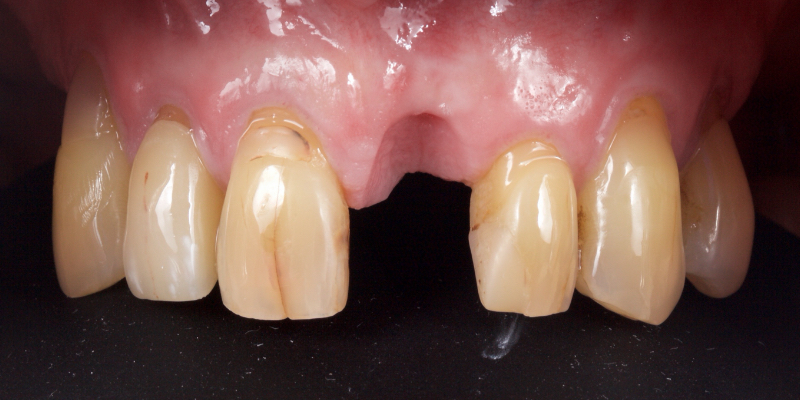

Take Arthur, a 76-year-old man who presented with a vertical root fracture of his upper left central incisor. His medical conditions precluded his request for an implant, so he agreed to the proposal for an adhesive bridge instead.

The tooth was extracted and for four months the pontic site was conditioned with a removable Essix-type of denture (Fig. 1).

An e.max (lithium disilicate), one-wing (adjacent central being the retainer) bridge was placed, which resulted in an acceptable outcome (Figs. 2-4) that was more timely and at a lower financial and biological cost to the patient than the implant Arthur initially thought he wanted.